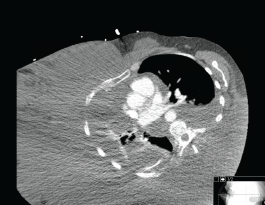

A 49-year-old Hispanic woman presented to the ambulatory medicine service for worsening oedema of her right upper extremity. Six years prior to presentation, she noticed painless swelling of her right thumb, which she initially attributed to an injury that occurred while working in a chicken-processing plant. She reported receiving repeated local injections of an unknown antibiotic in Honduras over the course of 2 weeks without relief. As time progressed, so did the swelling with extension from her hand to shoulder with eventual involvement of her right chest wall and hemithorax (Figure 1). Her medical evaluation at that time was extremely limited and included a complete blood count and an X-ray, both of which she reported were normal, and hence, no further workup was sought. Eighteen months before presentation to the clinic, she developed dyspnoea on exertion with occasional cough. She reported right arm and back pain from the significant swelling with associated right chest wall discomfort. Apart from postprandial nausea, she denied any fever, night sweats, weight loss, or lower extremity oedema. A computed tomography (CT) scan of the chest with contrast revealed soft tissue oedema without evidence of thrombus or obstruction in the venous system (Figure 2). Further evaluation for multiple infectious aetiologies, including tularaemia, coccidiodes, and malaria, were negative; however, she did have a positive purified protein derivative (PPD) test for which she received and completed latent tuberculosis treatment. Subsequent lymphoscintigraphy showed evidence of lymphatic obstruction at the level of the distal forearm and she was referred to a lymphedema clinic for compressive therapy. Her oedema continued to progress resulting in a large right-sided exudative chylus pleural effusion requiring thoracentesis. Fluid analysis for at that time was negative for malignancy and cultures were negative for acid-fast bacilli. She again presented two months later with dyspnoea and was found to have a re-accumulation of her pleural effusion at which time she underwent pleuroscopy with biopsy and pleurodesis with pleural drain placement. Although repeat pleural fluid analysis was negative for malignancy, thoracoscopy revealed a pleural space that was densely adherent in multiple locations with gelatinous, firm material. Pathological examination showed sections of very nodular neoplastic proliferation of small spindled to ovoid cells with eosinophilic cytoplasm and bland nuclei within a predominantly myxoid stroma. A ‘whorled’ cellular morphology was identified multifocally without mitotic figures or necrosis. Immunohistochemically, the tumour cells involved were positive for epithelial membrane antigen and progesterone receptor but negative for Ewing sarcoma break point 1 gene translocation, smooth muscle antigen, cytokeratin AE1/AE3, S100, calretinin, microphthalmia-associated transcription factor (MITF), and claudin 1 (Figure 3). The cytogenetics from the cell cultures of the pleural biopsy revealed complex chromosome translocations and deletions 45,XX,-6,inv(9)(p24q32)x2[14]/90,idemx2[3]/44,idem,dic(19;19)(q13.4;q13.4)[1]/90,idemx2,-6, 7, 11,dic(19;19)[1]/46,XX[1]. Surveillance magnetic resonance imaging (MRI) brain showed no intracranial or meningeal masses. Tissue specimens were referred to a sarcoma expert who identified it as an unusual variant of myxoid sarcoma that could not be classified. Chemotherapy was initiated with doxorubicin that she received every 21 days for 4 cycles. After one cycle of chemotherapy, she had a drastic improvement in her symptoms and physical appearance (Figure 4). Due to her poor performance status in addition to side effects from her prior regimen, her chemotherapy regimen was changed to gemcitabine. Unfortunately she continued to decline and ultimately opted for hospice care.

Figure 2. Axial CT chest demonstrating swelling of right hemithorax.